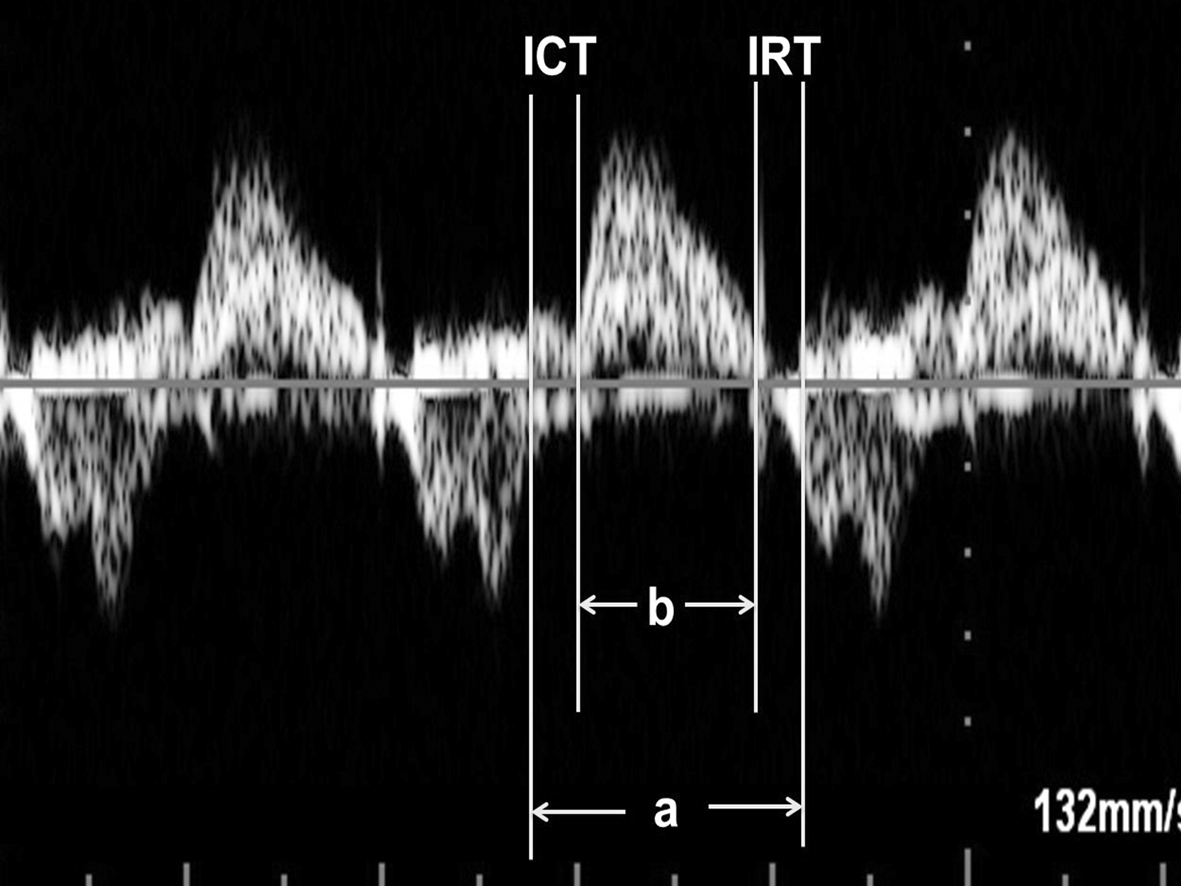

STDI检查可以通过等容收缩时间(ICT)、射血时间(ET)和等容舒张时间(IRT)计算心肌做功指数(MPI, Tei指数),并且通过STDI获得MPI较使用频谱多普勒检查获得MPI更可靠。

(1)MPI计算:①频谱多普勒检查心脏时,显示胎儿心脏五腔观,取样门放置在二尖瓣前叶远端和LV流出道结合部位,可以同时获得MVO血流和LV流出道血流,测量二尖瓣血流频谱前一心动周期A峰结束到下一心动周期E峰开始的时间间期,记为A,测量LV流出道血流时间为B,MPI = (A - B) / B;也有作者采取分别在MVO远端和AO瓣口获取血流频谱计算MPI的方法。②胎儿心脏TDI检查时测量显示Ea峰起点至Aa结束的时间(a)以及Sa持续时间(b),通过(a-b)/b获得MPI(图8、图9)。